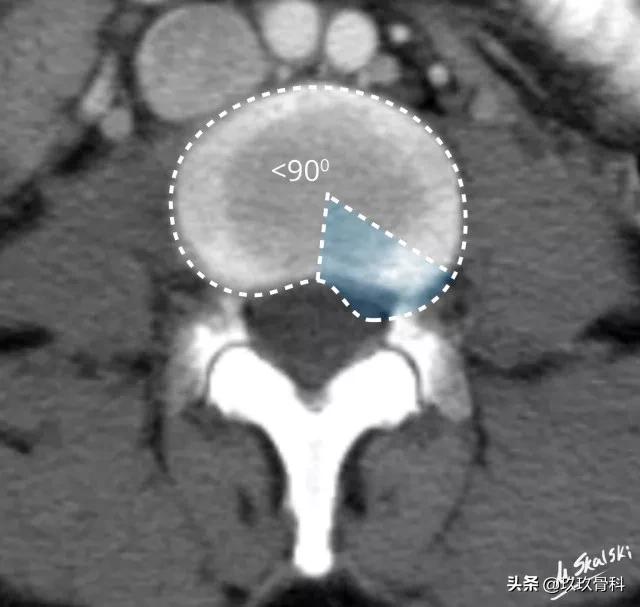

2. 椎间盘突出(Disc protrusion)

为髓核突入纤维环内但后纵韧带未破裂,表现为椎间盘局限性向椎管内突出。

图 4 椎间盘突出的影像学定义为突出部分小于椎间盘边缘的25%,并且基底部>突出部分的直径;突出椎间盘的两边与髓核的中心的夹角<90°